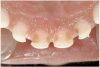

The characteristics of ECC (Figure 2) are:

1. It develops rapidly. Progression from the enamel into the dentin occurs in 6 months or less.

2. It affects the upper front teeth first. These teeth usually erupt at around 8 months of age.

3. Primary molars, which begin to erupt at about 12 months of age, are the next teeth to be affected.

4. Finally, the lower front teeth are affected when the disease becomes very severe.

One of the first clinical signs of the presence of ECC is the white-spot lesion—usually first seen on the maxillary incisors.26 The development and location of white-spot lesions are linked to:27

White spot lesions represent ECC in its early stage. During the early white-spot stage, the condition can be reversed by using preventive measures such as professionally applied fluoride varnish, gels, and foams.

As the condition worsens, white-spot lesions develop into larger caries lesions. The time frame from early decay to later decay can be as short as 6 to 12 months. At this point, the child may complain about toothache when extremely cold foods are eaten. As the caries process continues, the lesions will appear as brown/black collars around the gingival margin. The child will often begin to indicate the presence of pain.